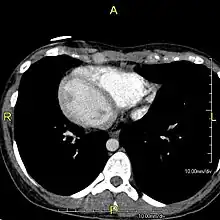

CT image showing dilated and thickened medium-sized airways (bronchiectasis) in a patient with Kartagener syndrome

Axial CT image showing chronic sinusitis in an individual with Kartagener syndrome